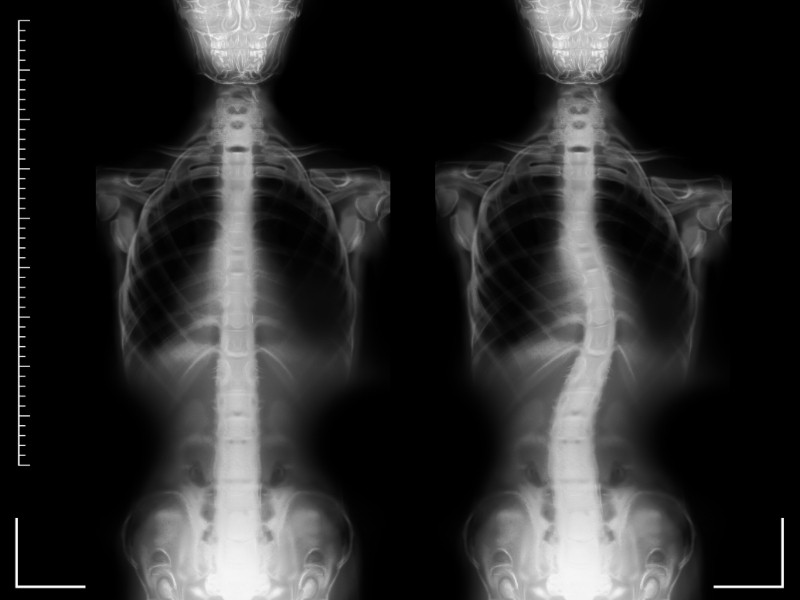

Ortopedik olarak en sık görülen omurga rahatsızlıkları skloyoz (omurganın yana eğilmesi), kifoz (omurganın öne eğilmesi), düzleşmiş omurga, omurga kırıkları ve kaymalarıdır.